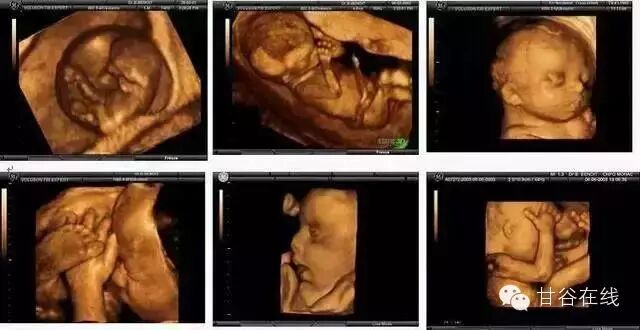

四 维 彩 超

甘谷首家四维彩超,骨密度检测,清晰度高,显示准确,受到了患者的一致好评。

四维彩色超声诊断仪出色的人体工程学设计,不存在射线、光波和电磁波等方面的辐射,对人体的健康没有任何影响。

提供了包括腹部、血管、乳腺、甲状腺等小器官、泌尿科、产科、妇科、胎儿等多领域、多方面的应用,是目前世界上最先进的彩色超声设备。

怀孕了就来善懿堂做四维彩超,这是甘谷准妈妈们都知道的事儿!这不仅仅是因为四维彩超可以准确的为孕妈妈进行身体检查,而且比起普通B超和三维彩超,四维彩超可谓是孕期检查项目中最“靠谱”的了。具体怎么个靠谱法呢?下面我们就一起来了解一下吧!

四维彩超

四维彩超就是四维成像技术(4D),能直观,立体显示人体器官的三维结构及动态、实时地观察立体结构。主要可以进行龄检测、分析胎儿的发育情况、筛查胎儿畸形等。

全面就行胎龄检测、分析胎儿的发育情况、筛查胎儿畸形等。是您育健康宝宝必须要做的一项检查!

四维彩超的筛畸范围:

1、神经系统:无脑儿、脑积水、小头畸形、脊柱裂及脑脊膜膨出。

2、泌尿系统:肾积水、多囊肾及巨膀胱、尿路梗阻。

3、消化系统:脐部肠膨出、内脏翻出、肠道闭锁及巨结肠等。

4、其它畸形:短肢畸形、联体畸形、先天性心脏病及畸胎病等。

四维彩超的检查时间:

单胎为怀孕第20—28周,双胞胎为18-22周。因为这个时期的胎儿大小适中,羊水量充足,比较容易采集到相对清晰的图像。

这就是四维彩超的魅力,让你领略肚子里面宝宝的魅力,善懿堂诊所为了更好的为患者服务,在我县率先开展了四维彩超、定量超声骨密度检测等检查,有效排除孕期胎儿畸形,为准爸妈们解除了困惑;精准检查骨密度,为骨质疏松患者带来了福音。

四维彩超的全称是四维彩色超声诊断仪,是目前十分受欢迎的孕期检查项目。它能够表面成像,可以更佳清晰的查出来胎儿的四肢发育是否畸形,脑膜膨出,是否有唇腭裂、脊柱裂等先天畸形,做到及时发现及时解决。